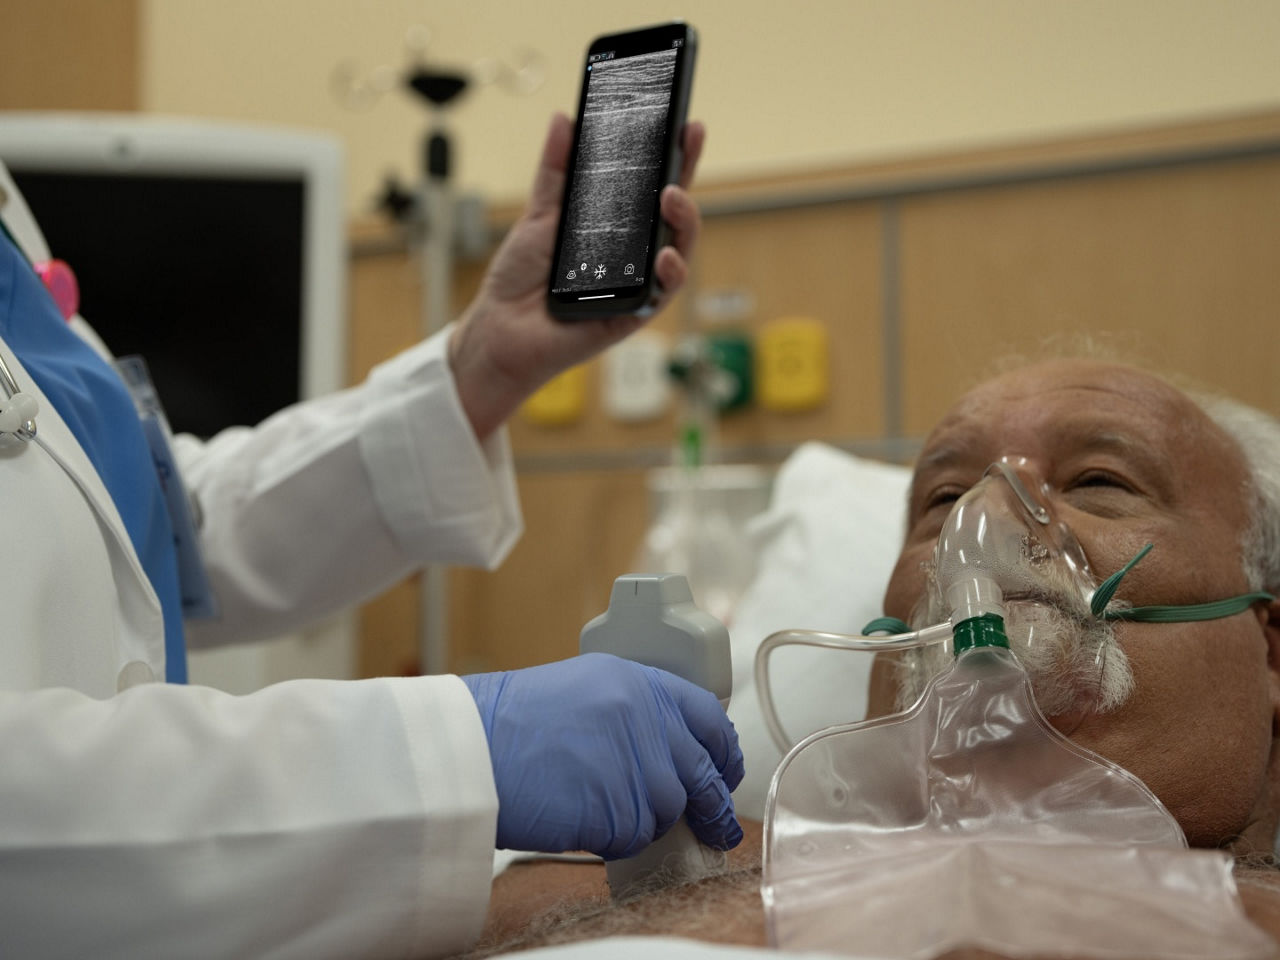

Enhanced mobility

Ultra portable and can be used in various critical care settings.

Reduced time

Handheld ultrasound can help reduce the time between diagnosis and treatment.